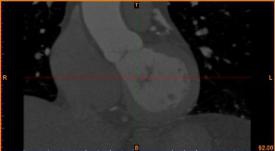

首先通過病人的心臟冠脈造影CT數據,獲取病人的心臟冠脈三維模型。

病人的冠脈造影CT數據                                              提取出的冠脈三維數據